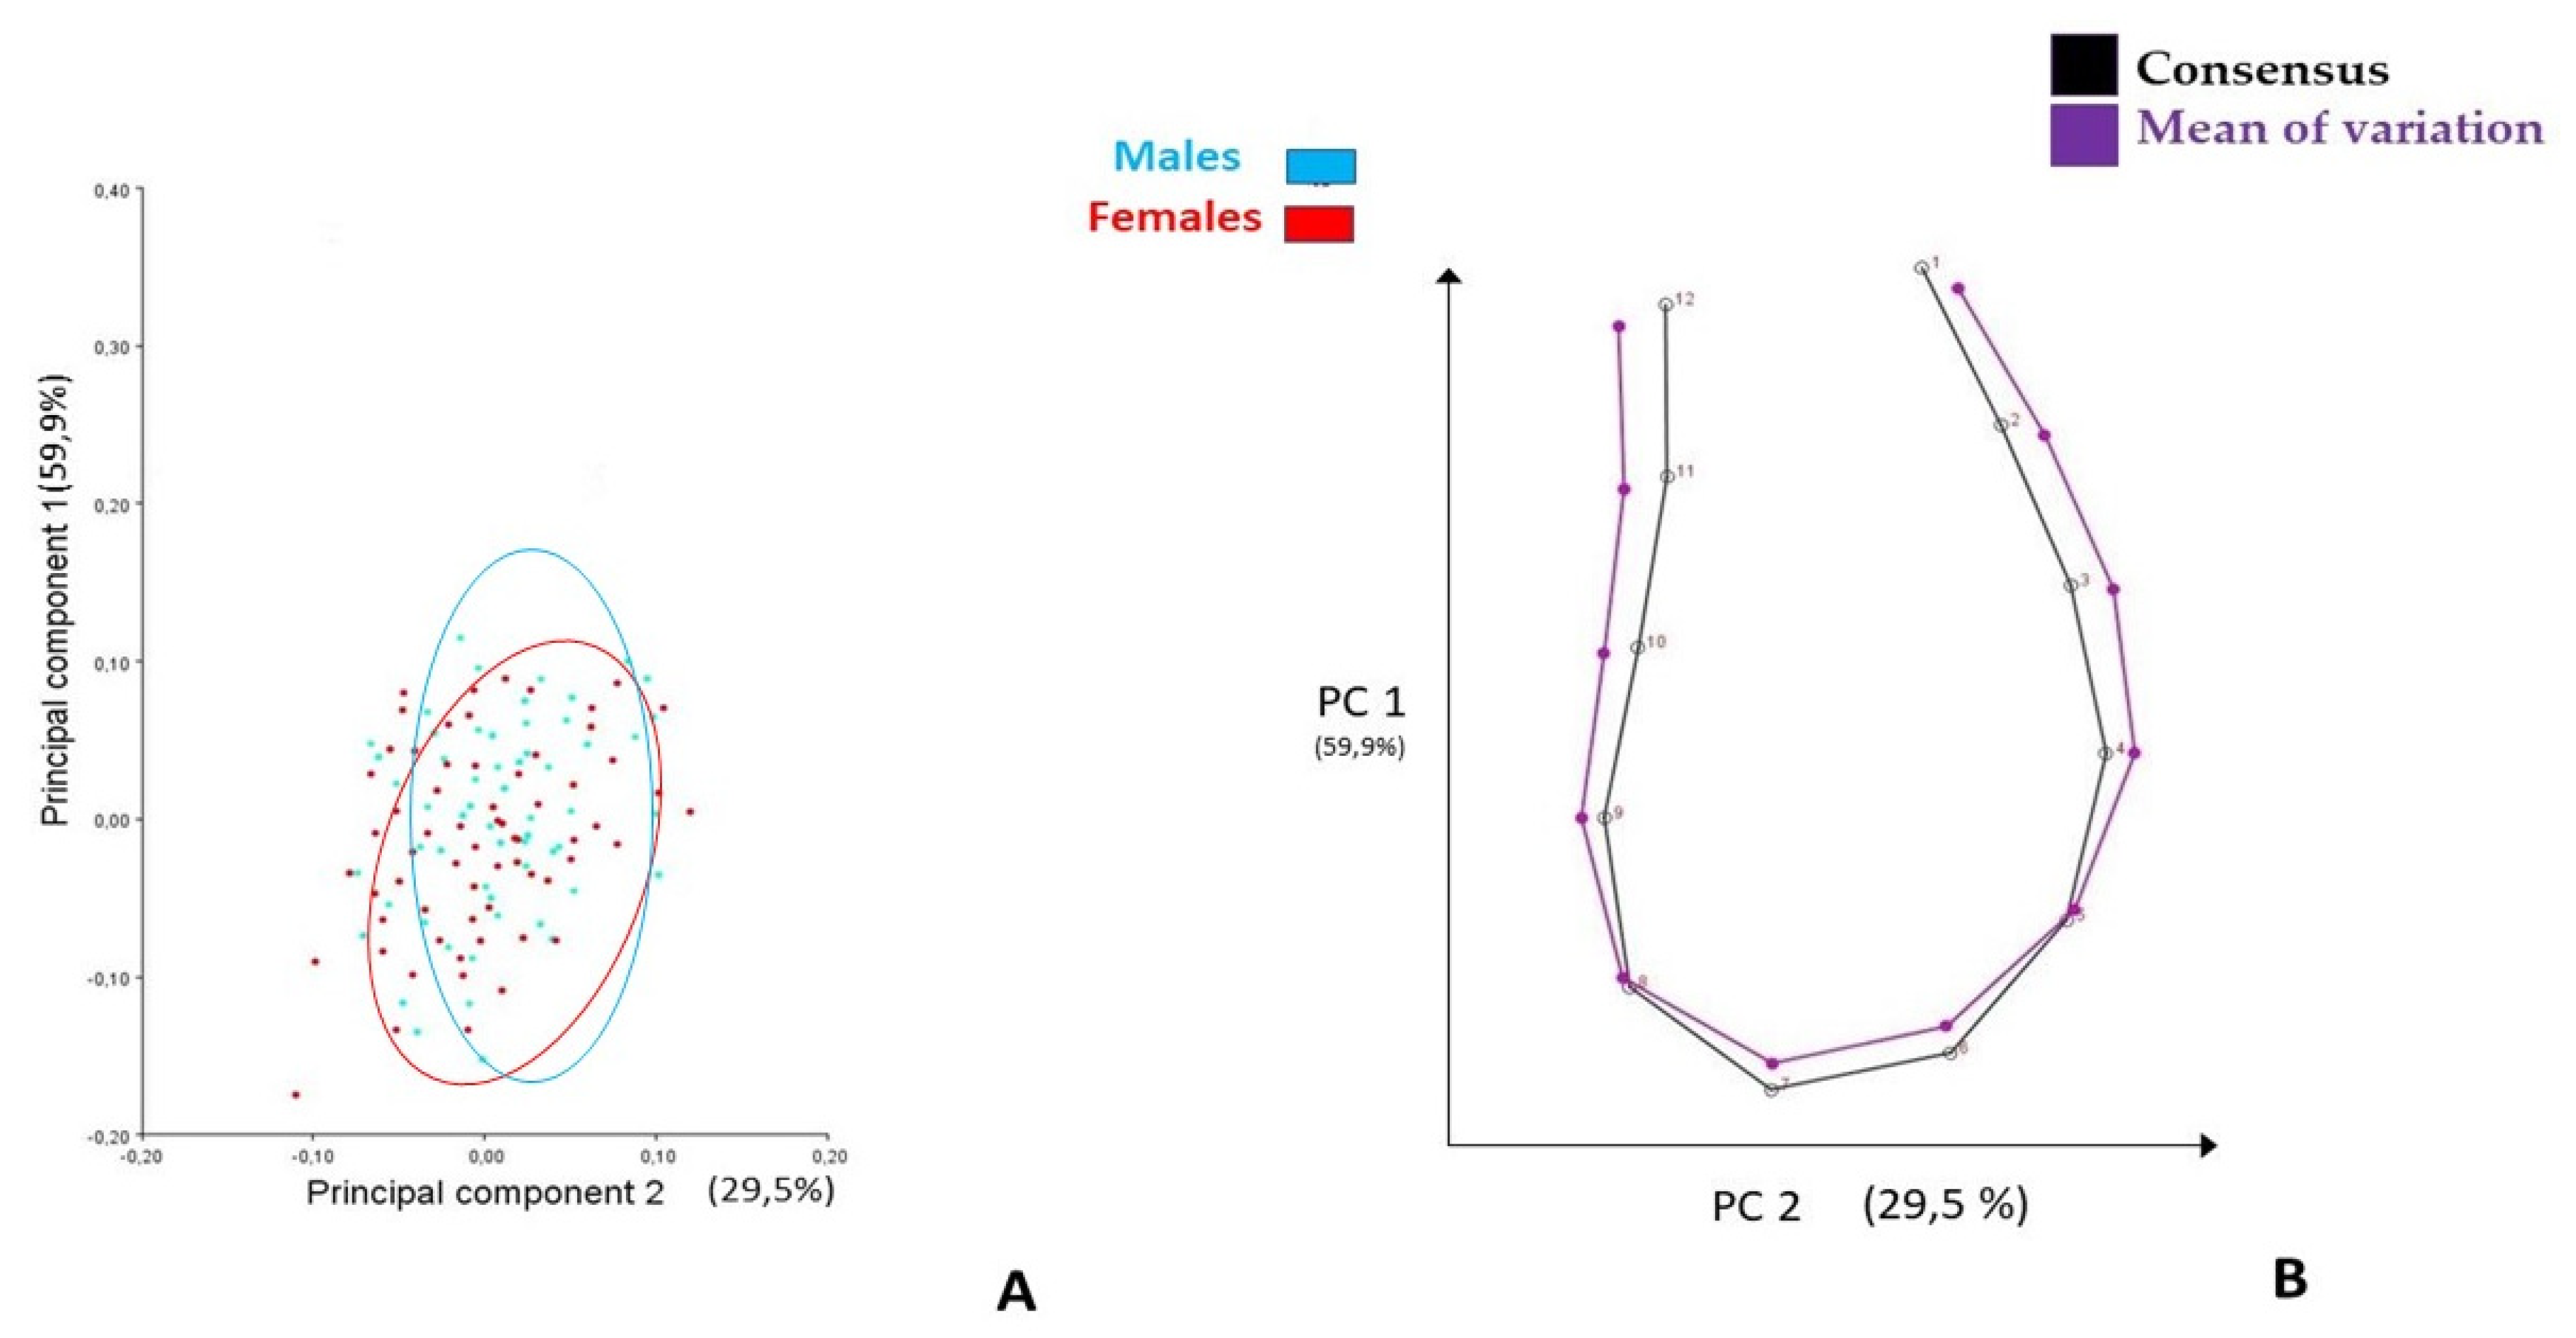

3.1. Generalized Procrustes Superimposition and PCA

4.1. Generalized Procrustes Superimposition and PCA